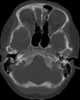

Expansile bone neoplasm

Aneurysmal bone cyst, abbreviated ABC, is an osteolytic bone neoplasm characterized by several sponge-like blood or serum filled, generally non-endothelialized spaces of various diameters.The term is a misnomer, as the lesion is neither an aneurysm nor a cyst. Signs and symptoms The afflicted may have relatively small amounts of pain that will quickly increase in severity over a time period of 6–12 weeks. [Source: Wikipedia ]